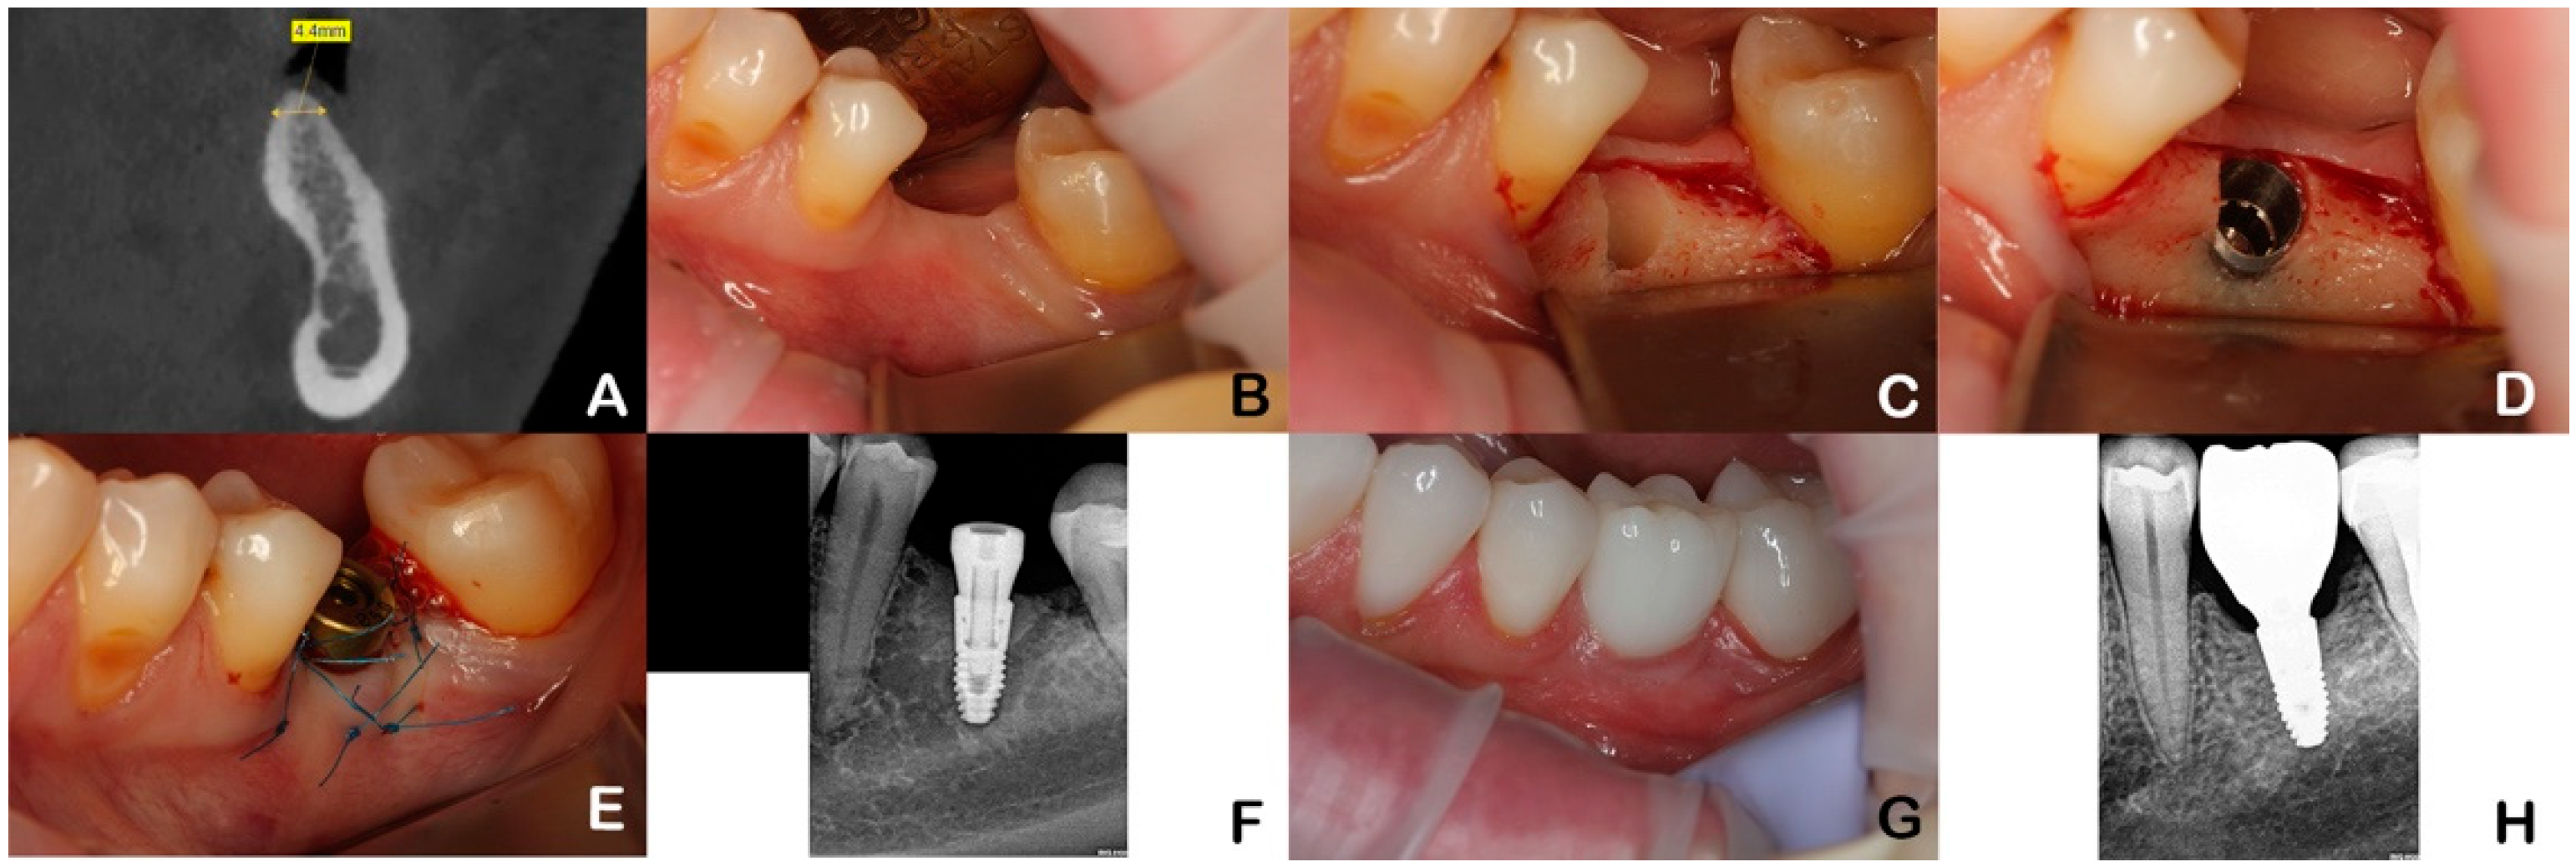

2.2. Intervention